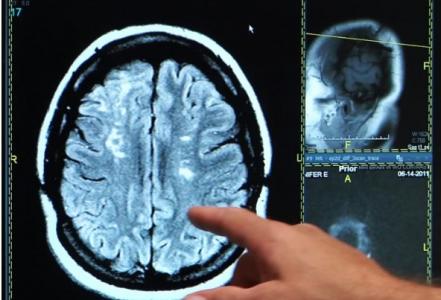

Cette intervention développée à l'Université de l'Alberta (Canada) basée sur une injection dans la colonne vertébrale se révèle efficace à restaurer les connexions entre le cerveau et la moelle épinière et à améliorer la récupération post-AVC. La preuve de concept apportée ici chez l’animal nécessitera de nombreuses recherches de confirmation et devra être encore testée chez l’Homme mais pourrait un jour jouer un rôle clé dans l'amélioration du rétablissement des victimes d'accident vasculaire cérébral (AVC).

L'AVC est la cause la plus fréquente d'incapacité chez les adultes. Le parcours typique de récupération implique une thérapie de réadaptation intensive. Au cours des premières semaines suivant un AVC, les patients ressentent des améliorations au fur et à mesure que le cerveau se reconfigure, mais finissent par atteindre un maximum et retrouvent rarement leurs capacités de départ.